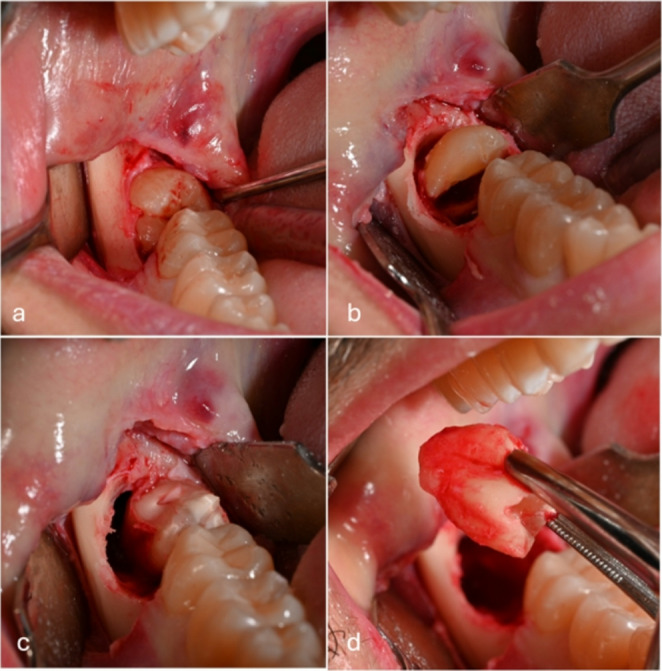

Materials and methods: The study was designed as a double-blinded, parallel group, randomized controlled clinical trial. 56 patients were divided into 2 groups: in the control group the socket was left to heal spontaneously, while the test group was treated with submucosal infiltration of i-PRF. Swelling was measured with a flexible ruler using the diagonals joining Trago and Pogonion, Gonion and labial cleft. The swelling was calculated as the sum of these diagonals before surgery, on day 3 and 7. Pain was assessed by VAS scale until the 7th postoperative day. Surgical wound healing was evaluated by the Healing Index by Landry on 3, 7 ,14 and 21st day postosperatively. The relation between duration of intervention and total swelling was also evaluated.